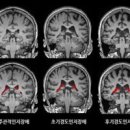

자가포식 기능 회복 과정이 형광으로 표시돼 있다. 출처=저로사이언스(2025)/스프링거 실험 설계와 주요 발견 연구진은 알츠하이머 증상을 보이는 노령 생쥐의 신경세포에 니코틴아미드와 EGCG를 투여했다. 24시간 뒤 형광 추적 기법으로 GTP 수준을 관찰...